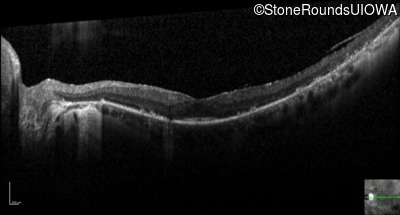

Optical Coherence Tomography - Right - 20/20

Exemplar / OCT Stack

OCT Stack